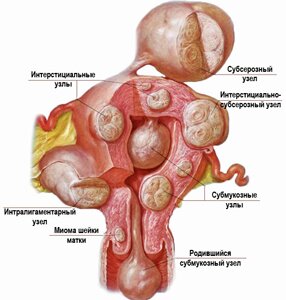

Фибромиомой называется одиночный узел или скопление доброкачественных образований из Далее...